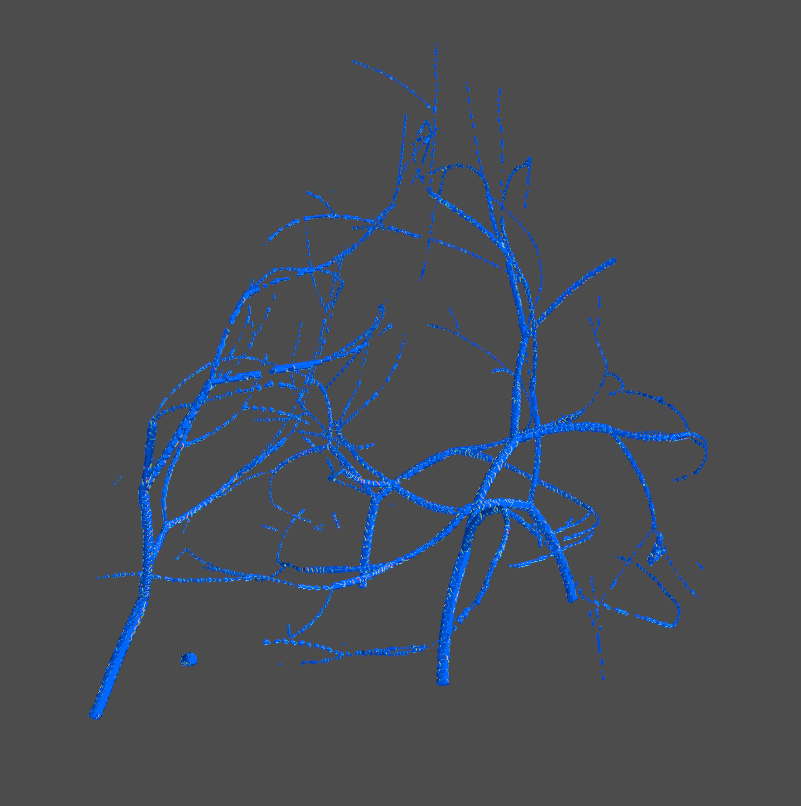

2.2 Persistence Cycles and Their Computation

Although the persistence diagram has been used for topological analysis in various dataset [27, 74, 78], it only records limited information, i.e., the times at which these topological structures appear/disappear. We hypothesize that a detailed geometric realization of these topological structures can be crucial for learning from images. To this end, we propose extracting these topological structures and integrating them into the learning process. As shown in Fig. 3, we extract loops (blue) to denote 1D topological structures and bubbles (red) for 2D topological structures. These structures are then used to guide the attention mechanism within the neural network.

Upon selecting topological structures based on persistence, we use the voxels from their representative cycles to craft topological masks. We generate two distinct binary 3D masks that represent the 1D and 2D topological cycles. Empirical observations have revealed that a ”soft” mask conveys more detailed information. Rather than directly employing binary masks, the foreground voxels are populated with their inherent image intensity values. Given that all masked MRIs are padded to a size of , we subsequently produce two topological masks, and , which pertain to the 1D and 2D topological cycles, respectively.

Fig. 7 presents topological structures from three distinct perspectives, showcasing one representative sample each for cases with and without pCR. We observe that the 1D and 2D structures are sparser in the case with a pCR response, while they appear denser in the non-pCR case. Examining the corresponding MRI images, we notice that the breast with pCR exhibits scattered fibroglandular tissue and minimal background parenchymal enhancement. In contrast, the non-pCR breast displays more heterogeneous fibroglandular tissue accompanied by moderate background parenchymal enhancement. This observation suggests that the topological structures may be capturing the intricate fibroglandular structure, potentially serving as an indicator of treatment response.

We also analyze the topological characteristics of two patient populations by comparing their birth times, which indicate the threshold at which a cycle first appears. Given our use of the inverse image in the experiments, denoted as , meaning the birth time essentially corresponds to times the brightness of a structure. For each population (pCR and non-pCR), we compute the Cumulative Density Function (CDF) curve using the average birth time from all samples in that group. As depicted in Fig. 7 (right), the CDF for pCR patients (in red) compared to non-pCR patients (in blue) reveals that topological structures in pCR patients’ tissues tend to be less bright or distinguishable than those in non-pCR patients, an observation that aligns with our qualitative assessments. To statistically validate these differences in CDFs, we conduct a Kolmogorov-Smirnov test [45]. The resulting -value of indicates a significant disparity in the birth time distributions between the pCR and non-pCR patient groups.

We employ the Grad-CAM implementation from the M3d-CAM library [22] to visualize attention maps following the Topology-Guided Spatial Attention (TGSA) module in the best-performing TopoTxR model. For comparison, we modify the TopoTxR model to exclude the TGSA module, utilizing a single 3D CNN branch that processes only raw MRI data. In this setup, Grad-CAM is applied after the third convolution layer to visualize attention maps, as depicted in the second row—’CNN Grad-CAM’ in Fig. 8. Conversely, the attention maps from our proposed model are shown in the first row—’TGSA Attention.’ In Fig. 8, we provide a comparative analysis of the attention maps from two views, showcasing one representative sample each for cases with and without pCR. This comparison highlights that the TGSA module effectively directs the CNN’s focus to specific, biologically relevant regions, as delineated by topological structures. Conversely, the model lacking topology information shows a more scattered and dispersed attention distribution across the MRI volume. It is interesting to note that the topological structures appear sparser in cases with a pCR, whereas they are denser in cases without pCR.